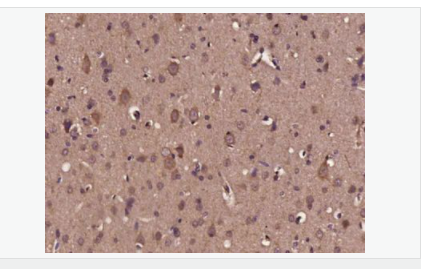

| 產(chǎn)品介紹 | Neurotrophins function to regulate naturally occurring cell death of neurons during development. The prototype neurotrophin is nerve growth factor (NGF), originally discovered in the 1950s as a soluble peptide promoting the survival of, and neurite outgrowth from, sympathetic ganglia. More recently, three additional structurally homologous neurotrophic factors have been identified. These include brain-derived neurotrophic factor (BDNF), neurotrophin-3 (NT-3) and neurotrophin-4 (NT-4), also designated NT-5. These various neurotrophins stimulate the in vitro survival of distinct but partially overlapping populations of neurons. The Trk A receptor is the preferential receptor for NGF, but also binds NT-3 and NT-4. The Trk B receptor binds equally well to both BDNF and NT-4 and to a lesser extent NT-3, while the Trk C receptor only binds NT-3. BDNF promotes the survival of neuronal populations that are all located either in the central nervous system or directly connected to it. Belongs to the NGF-beta family. Function: During development, promotes the survival and differentiation of selected neuronal populations of the peripheral and central nervous systems. Participates in axonal growth, pathfinding and in the modulation of dendritic growth and morphology. Major regulator of synaptic transmission and plasticity at adult synapses in many regions of the CNS. The versatility of BDNF is emphasized by its contribution to a range of adaptive neuronal responses including long-term potentiation (LTP), long-term depression (LTD), certain forms of short-term synaptic plasticity, as well as homeostatic regulation of intrinsic neuronal excitability. Subunit: Monomers and homodimers. Binds to NTRK2/TRKB. Subcellular Location: Secreted. Tissue Specificity: Brain. Highly expressed in hippocampus, amygdala, cerebral cortex and cerebellum. Also expressed in heart, lung, skeletal muscle, testis, prostate and placenta. Post-translational modifications: The propeptide is N-glycosylated and glycosulfated. DISEASE: Defects in BDNF are a cause of congenital central hypoventilation syndrome (CCHS) [MIM:209880]; also known as congenital failure of autonomic control or Ondine curse. CCHS is a rare disorder characterized by abnormal control of respiration in the absence of neuromuscular or lung disease, or an identifiable brain stem lesion. A deficiency in autonomic control of respiration results in inadequate or negligible ventilatory and arousal responses to hypercapnia and hypoxemia. CCHS is frequently complicated with neurocristopathies such as Hirschsprung disease that occurs in about 16% of CCHS cases. Similarity: Belongs to the NGF-beta family. SWISS: P23560 Gene ID: 627 Database links: Entrez Gene: 627 Human Entrez Gene: 12064 Mouse Omim: 113505 Human SwissProt: P23560 Human SwissProt: P21237 Mouse Unigene: 502182 Human Unigene: 1442 Mouse Unigene: 11266 Rat Important Note: This product as supplied is intended for research use only, not for use in human, therapeutic or diagnostic applications |